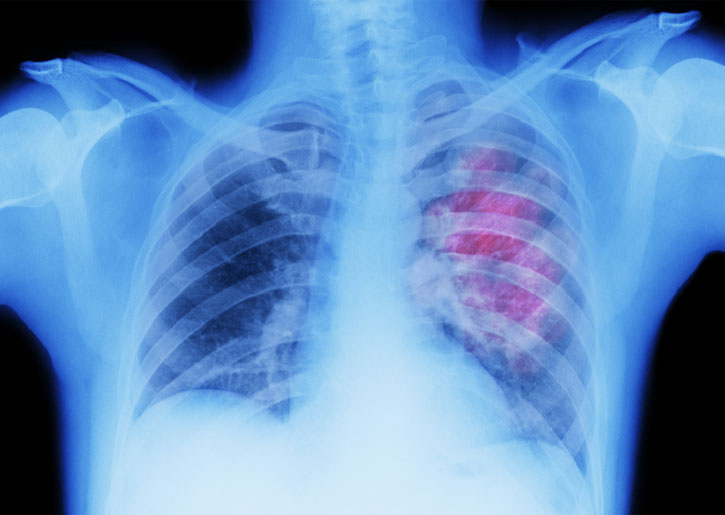

ويظل سرطان الرئة السبب الرئيسي لحدوث السرطان والوفيات في جميع أنحاء العالم. وفي عام 2022، تم تشخيص نحو 2.5 مليون شخص بالمرض.